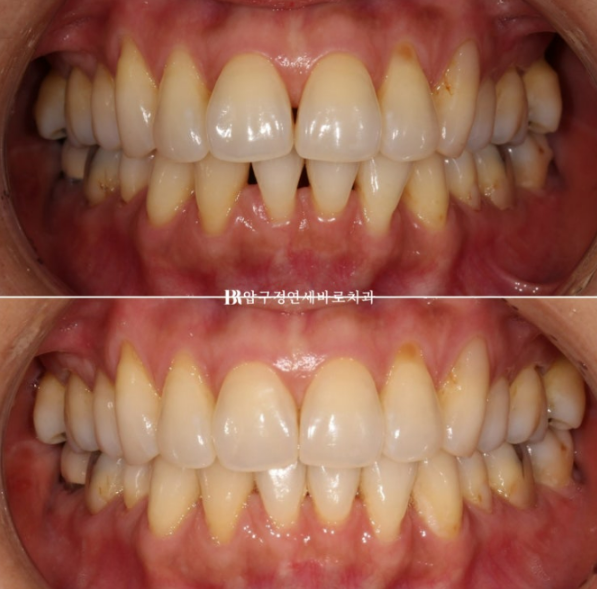

23.04~23.08

23.04

앞에서 봤을 때 블랙트라이앵글이 크죠

특히 앞니 두개가 유난히 커보입니다.

치료 시작 2개월 후 모습입니다.

블랙트라이앵글이 벌써 많이 줄었습니다.

비스듬한 측면에서 봤을 때에도 블랙트라이앵글이 많이 줄어든 것이 보입니다.